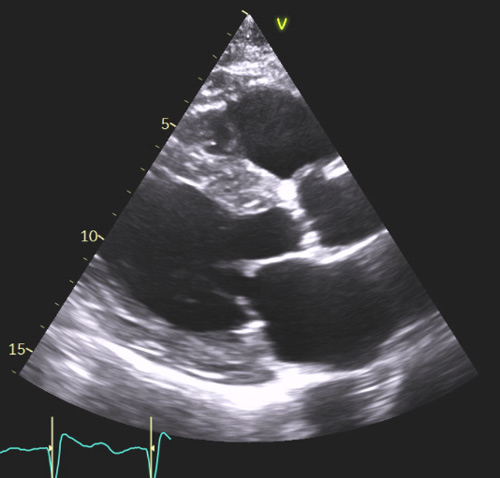

L’atteinte cardiaque secondaire à une amylose se présente généralement sous forme d’hypertrophie biventriculaire avec une hypertrophie ventriculaire gauche le plus souvent concentrique ou diffuse (Figure 1a), qui peut cependant parfois être modérée (12-13 mm). Généralement non obstructive, cette hypertrophie peut prédominer au niveau du septum interventriculaire et même prendre parfois l’aspect d’une cardiomyopathie hypertrophique sarcomérique. Il convient donc de la suspecter devant toute hypertrophie ventriculaire gauche (VG), surtout si celle-ci est concentrique ou diffuse, et si elle s’associe à d’autres éléments comme une hypertrophie de la paroi du ventricule droit (VD) (épaisseur de paroi >5 mm lors de la mesure réalisée en incidence sous-costale) (Figure 1b) avec dysfonction systolique assez fréquente sans être systématique.

Figure 1 : Aspects morphologiques échocardiographiques typiques d’amylose cardiaque

a- HVG concentrique diffuse avec dilatation biatriale